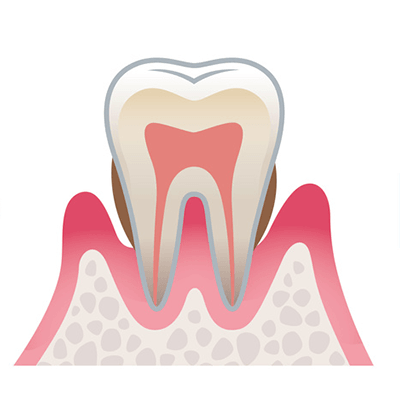

軽度歯周病

歯ぐきに炎症が起こり、少しずつ腫れが出てきます。痛みはありませんが、歯みがきのときや硬いものを食べたときに出血することがあります。

見た目の特徴

歯ぐきが赤く腫れ、歯と歯の間にプラーク(歯垢)がたまりやすくなります。

中度歯周病

炎症が歯ぐきだけでなく、歯を支える骨にまで広がった状態です。骨が少しずつ溶け始め、歯がグラついたり、口臭が気になったりします。歯が浮いたような違和感を感じることもあります。

見た目の特徴

歯ぐき全体が赤く腫れ、色が濃く変化していきます。